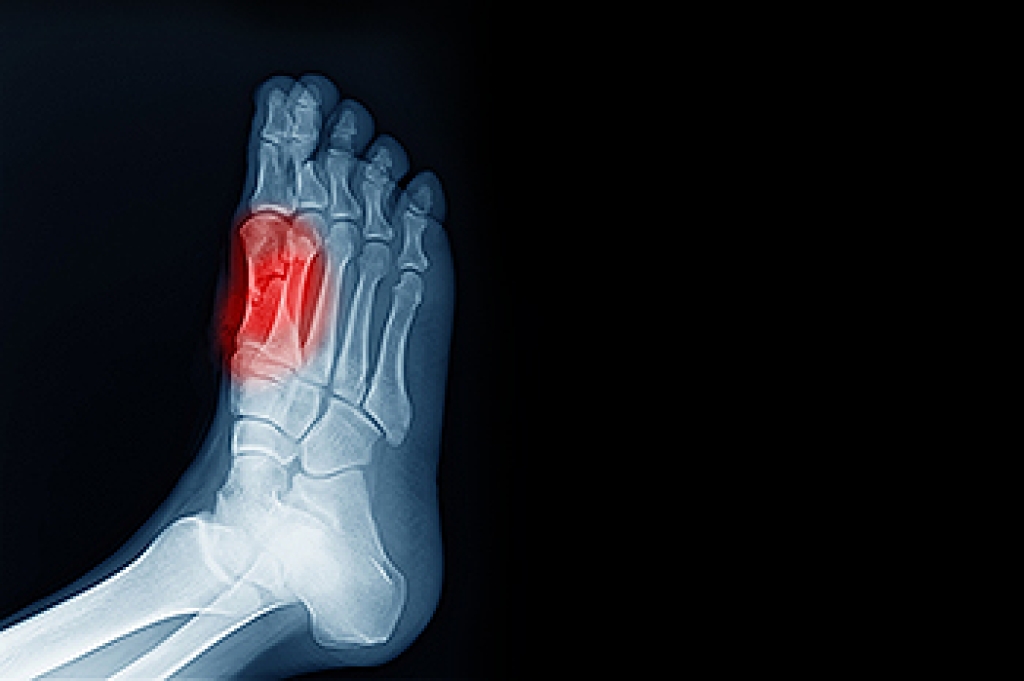

Foot ailments often signal underlying health issues that require attention. Conditions like dry, flaking skin on the feet might suggest fungal infections such as tinea, or could point to dermatitis conditions like eczema or psoriasis that are often linked to stress. Morning foot pain may result from wearing improper footwear or increased physical activity, but persistent pain could indicate more significant problems, like plantar fasciitis or other structural concerns. Cold feet might suggest poor circulation, which can have broader and more serious implications for vascular health. Clawed toes, commonly caused by wearing tight or pointy shoes, can also be associated with nerve damage or improper footwear sizing. Swollen feet, or edema, may result from poor venous circulation, indicating potential vascular or systemic health issues. A podiatrist can address underlying causes and recommend custom orthotics, footwear adjustments, or other treatment to improve your foot health. If you have unexplained foot or ankle issues, it is suggested that you schedule an appointment with a podiatrist for an exam and diagnosis.